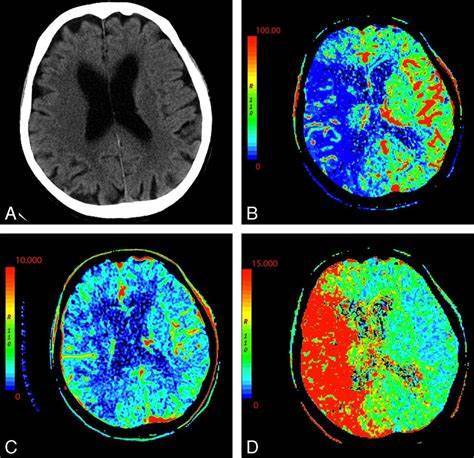

What is a Watershed Infarct?

Watershed cerebral infarctions (WI) , also known as border zone infarcts occur at the border between cerebral vascular territories where the tissue is furthest from arterial supply and thus most vulnerable to reductions in perfusion.